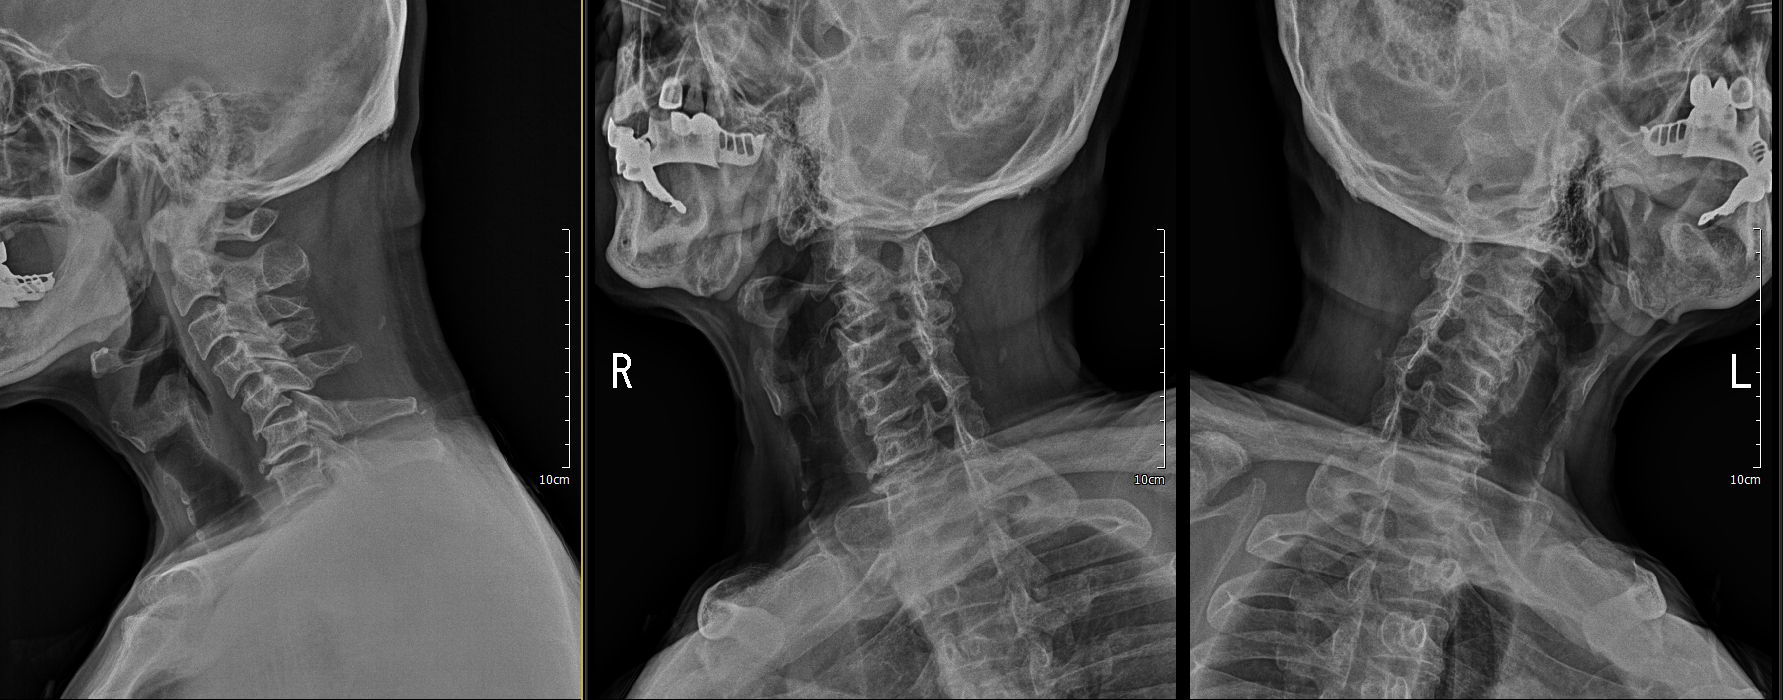

x ray 측면에서 보면 경추 5/6 후관절 탈골이 확인이 됨.